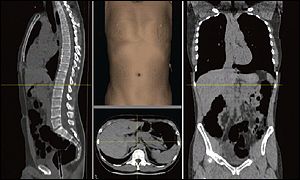

Body scans are a non-invasive and an early disease detection program with a unique tracking capability. The 3-dimensional computerized journey through the body helps with early detection of the following diseases: